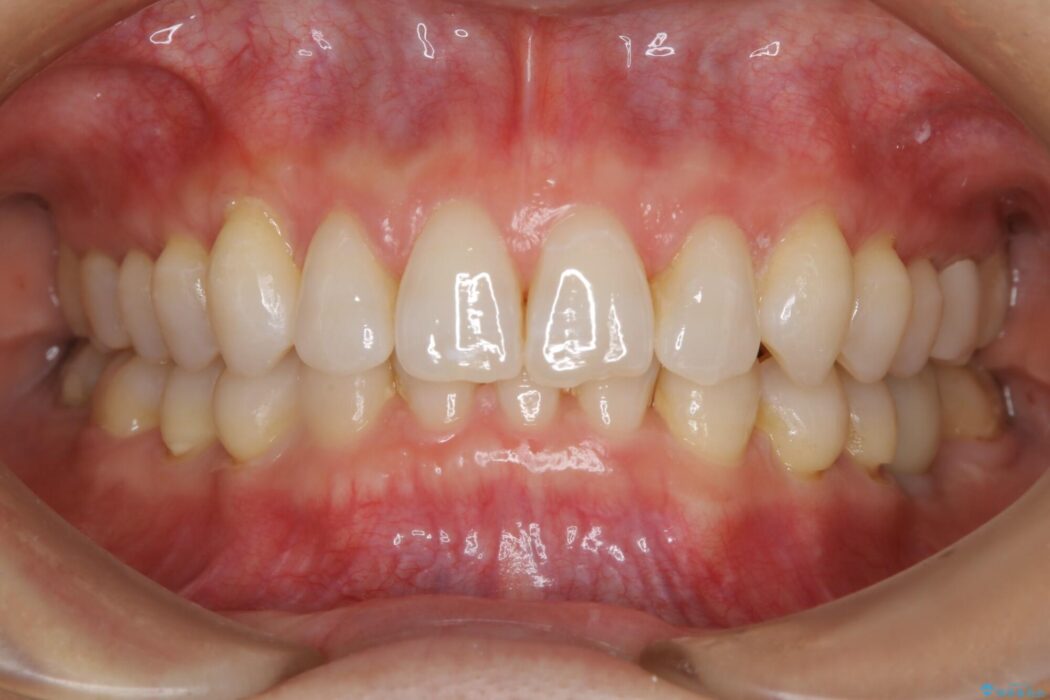

噛み合わせも改善され、一番最初の目的であった歯列もきれいに整いご満足いただけました。